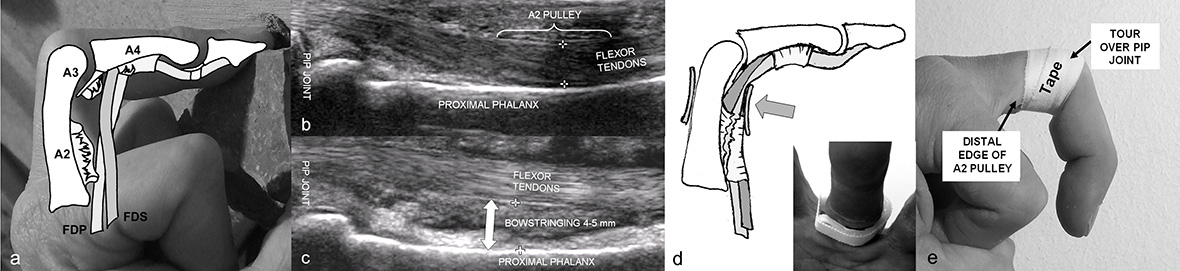

Climbing of particularly difficult routes with small holds leads to very high impact-forces on the finger bones and joints with impressive changes of the thickness of the cortices (fig. 3) [32]. Whether rock-climbing leads also to a degenerative arthritis of the finger joint has already been debated and investigated by different authors [33–35]. They described radiographical changes of finger joints of long-term climbers such as osteophytes, subchondral sclerosis and joint space narrowing. Nevertheless, none of those authors could show clear evidence of an increased rate of degenerative arthritis compared to an age-matched group of non-climbers [33–35]. In these studies the radiographs were mostly performed in an anterior-posterior view and the changes of the joints were assessed according to the Kellgren and Lawrence [36] or the Altmann score [37]. We conducted a study [38] where we investigated the anterior-posterior and the lateral views of the fingers in a group of 31 Swiss performance sport climbers. The mean of years of climbing was 20 years and the mean of the highest reached sport climbing level was 8b redpoint (French grade, corresponding to UIAA grade 10). Almost all of the climbers had little or no symptoms in the finger joints but up to 84% showed osteophytes at the PIP-joints and up to 68% in the DIP-joints. According to the Kellgren and Lawrence score 6 climbers (19%) had signs of an osteoarthritis (significant) whereas the age-matched non-climbing-group had practically no signs of radiological changes in the finger joints. We observed that in the lateral views (fig. 3) the climbers showed even more impressive osteophytes in the DIP and PIP joints. However there were almost no other apparent changes such as subchondral cysts, osteolysis or joint space narrowing. Most of the climbers concerned had performed bouldering at a high level and were older than 35 years. These climbers reported rare episodes of slight pain and stiffness on the dorsal side of the joints when hitting hard objects or after climbing intensively with the crimp-grip-position. This can be explained by an irritation of the dorsal side of the joint capsule by the osteopytes [39]. The pain usually disappears after 3–5 weeks, sometimes corticosteroid-injections are necessary and very rarely such an osteophyte has to be removed. Even when calcified parts or osteophytes are broken off and freely move in the joint, they are taken up by the joint capsule and become asymptomatic after several weeks.

Figure 3

Osseous adaptations of climber’s distal and middle phalanx compared with a non-climbers bones (A); epiphyseal thinning (B, left), epiphyseal fracture (B, middle) in an adolescent climber, strict avoidance of crimp grip let the fracture heal without a joint surface incongruity or axial deviation (B, right); lateral view of the fingers of a 38-year-old world class boulderer, almost every joint shows osteophytes and calcifications of the capsule, joint space narrowing, a main sign of osteoarthritis however is not apparent.

We still do not know the long-term effects of sport climbing to the finger joints. The oldest climbers performing the sport at such a high level are generally not older than early fifties. However, it seems that the changes observed have arisen through adaptation and do not show the same pattern of the common inherited degenerative arthritis (poly-arthrosis).

In order to prevent the development of these changes, we recommend not using a pronounced crimp-grip-position with a flexion of the PIP-joints to more than 80–90° and trying to keep the DIP-joint always flexed to about 5–15°. This is the position (85° flexion) where the PIP joint generates maximal flexion torque [40, 41]. By doing so, the joints are loaded in a midway-position whereas the joint contact area remains as large as possible. The full crimp-grip where the thumb overlays the index finger should therefore be avoided wherever possible.

Particularly in young adolescent climbers or in children, the full crimp-grip-position has to be avoided. The growth plates of the finger bones are not closed until the age of 17–19 years, are the weakest structures of the finger, and are most susceptible to injuries [42, 43]. In the full crimp-grip-position a shift of the middle phalanx results in a very high load proximal to the dorsal part of the base of the middle-phalanx. This may lead to growth-plate overload, consolidation and partial necrosis and finally to growth plate fracture (Salter-Harris II fracture, fig. 3). Premature partial or complete closure of the growth-plate with uneven or interrupted further growth of the finger bone ending up in a considerable axial-deviation or foreshortened finger may follow. Even complete destruction of the joints and early degenerative changes are possible. As soon as pain without obvious trauma in the PIP-joints is apparent in an adolescent, the crimp-grip-position should not be tolerated at all until the pain disappears or the growth-plates have closed at the age of 17–19 years. Regular radiographic controls are mandatory.